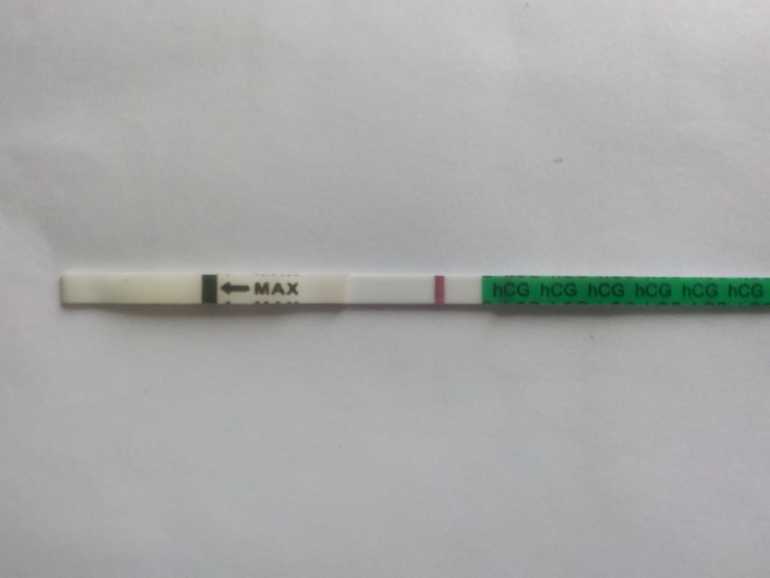

замочила только что....и снова непонятки...что это? реагент или проклевывается что то?....обеденный тест был вот таким

замочила только что....и снова непонятки...что это? реагент или проклевывается что то?....обеденный тест был вот таким

размылся весь как брак.....но я не передерживала....

Посмотрела ,да....тоже размыт был у вас....спасибо ....буду ждать утра...посмотрим что это,реагент или моя ляля....

я наоборот на нижнем и увидела....сначала а потом побежала в аптеку за ещё одним...на нижнем четкая полоска но очень бледная,плохо виждно а вот вечерний похож на реагент..растекся весь

Есть вроде на обоих но тесты тупаки конечно

да? а размытый весь ...не знаю с чего? не передерживала....завтра утром посмотрим....самой интересно